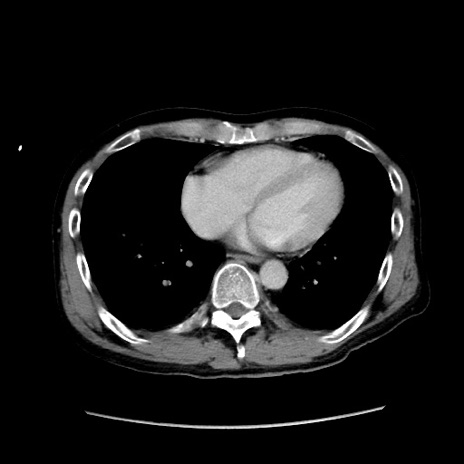

冠状断像

【症例】40歳代 男性

【主訴】腹痛

【現病歴】4時間ほど前に電車に乗車中に臍部上より腹痛出現。徐々に増悪し起立困難となり、救急外来受診。生ものは数日食べていない。今朝お雑煮を食べた。

【身体所見】BT 36.8℃、BP 117/84mmHg、HR 91/min、SpO2 97%、苦悶様、腹部:臍上部広範囲圧痛あり、反跳痛±

【データ】WBC 8100、CRP 0.03